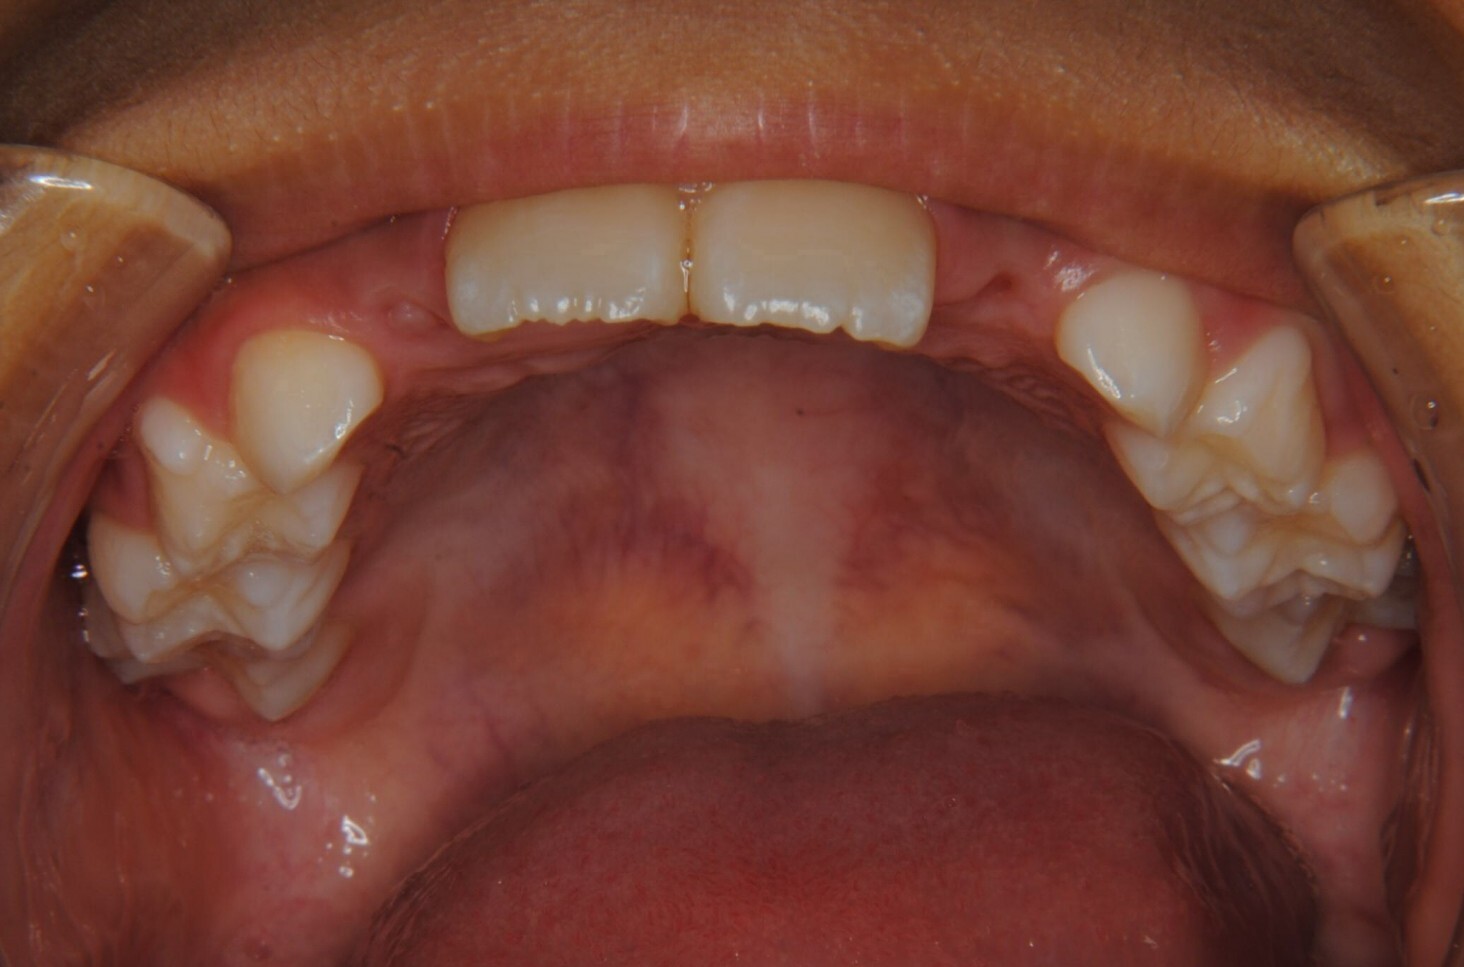

②診断名:Ⅰ級叢生

③年齢:初診時(左写真)8歳6か月、終了時(右写真)11歳4か月

④治療に用いた主な装置:拡大床

⑧リスクと副作用:特に大きなリスクや副作用はありませんでした。拡大床装着直後は違和感があったようですが、特に痛みを感じることなく6.5mmまで拡大できました。その後永久歯への生え変わりも順調で、ほぼ正常な咬み合わせになりました。この後11歳4か月まで観察し、7番目の奥歯である12歳臼歯がきちんと咬んだので終了となりました。